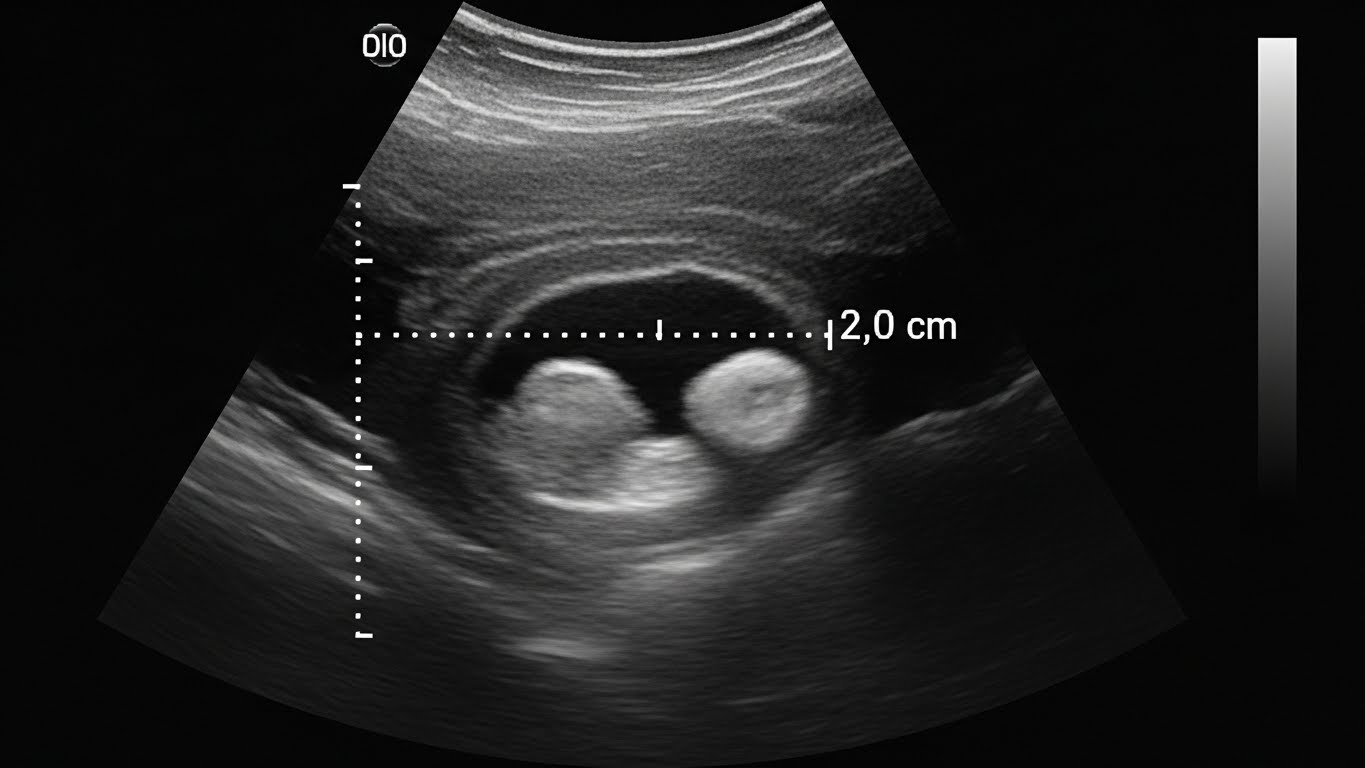

- 갑상선 초음파 검사

- 갑상선 결절, 크기, 염증 여부 확인